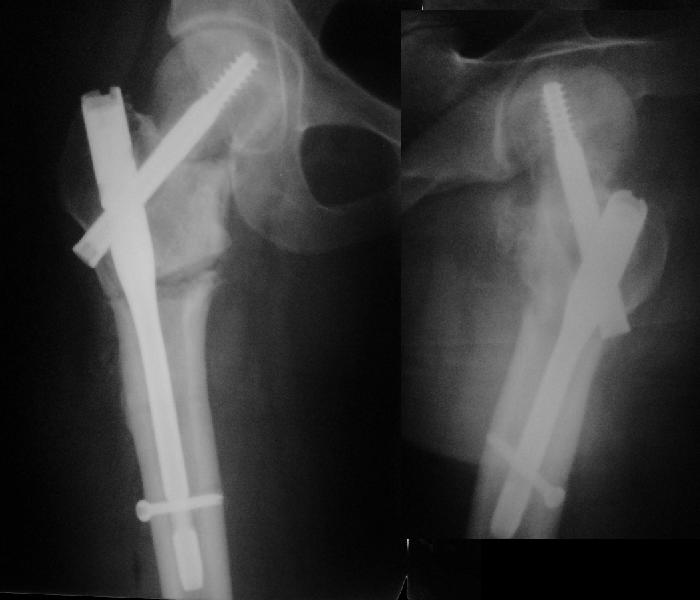

Никто не обратил внимания, что конструкция-то вся "развинчена" - вывернулся винт из шеечного винта, пластина не прилегает к диафизу. Резорбция кости вокруг шеечного винта не позволит как-нибудь надежно синтезировать вальгизирующую остеотомию, а в случае неудачи сама остотомия осложнит последующее эндопротезирование. Поэтому, думаю, что лучшим вариантом будет синтез аутокостью + канюлированные винты (дабы избежать кокситной повязки).

Похоже удалось провести шеечный винт мимо старого канала, и вальгус, вроде, удался. Только хороший-ли контакт фрагментов в зоне остеотомии? Действительно - жизнь покажет.